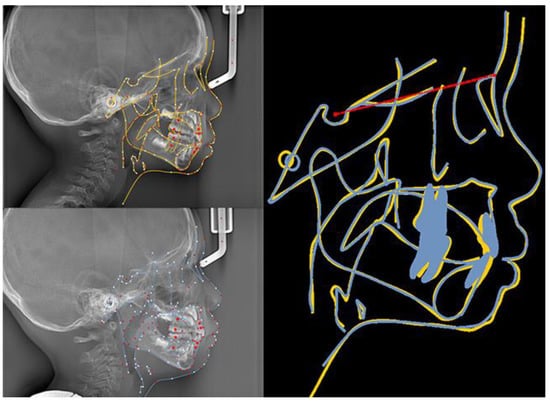

The patient and his parents allowed the use of his medical records, photographs and radiographs in this research. Prior to the initiation of therapy, panoramic and lateral cephalometric films were obtained. The panoramic radiograph showed swelling in the bilateral nasal mucosa (Figure 4). A mild skeletal Class II sagittal relationship (ANB = 5.4°) and large mandibular plane angle (SN-MP = 39.8°) were indicated in the pre-treatment cephalometric film (Table 1). Meanwhile, his hyoid (MP-H) rested lower than normal (16.8 mm, mean normal = 14.2). In addition, he had a hyperdivergent growth pattern (facial height index, S-Go/N-Me = 57.9%). The airway width assessment showed that he had a limited nasopharyngeal airway gap and expanded oropharyngeal segments (data shown in Table 1). His adenoids were diagnosed with moderate hypertrophy (Figure 5) with an A/N of 64.5% [11,12], which was derived from an adenoidal–nasopharyngeal ratio (AN ratio) via linear measurements using lateral radiographs of the nasopharynx according to Fujioka et al. and Zou. et al. [11,12]. Considering that adenoids in children are physiologically enlarged between 2 and 12 years of age, Zou proposed that an A/N ratio of 0.60 should be considered as normal; 0.61–0.70 is considered as moderate hypertrophy; ≥0.71 is considered as pathological hypertrophy [12]. The digital models’ STL files were uploaded to the Geomagic Studio 12.0 software (Research Triangle Park, NC, USA) for measurement (Figure 6 and Figure 7). The statistics concerning the widths of the dental arch and basal skeletal, as well as the height, surface area and volume of the palatal, are displayed in Table 2.

Figure 18. The initial and final lateral cephalograms and overlapping graphs of cephalometric tracing.